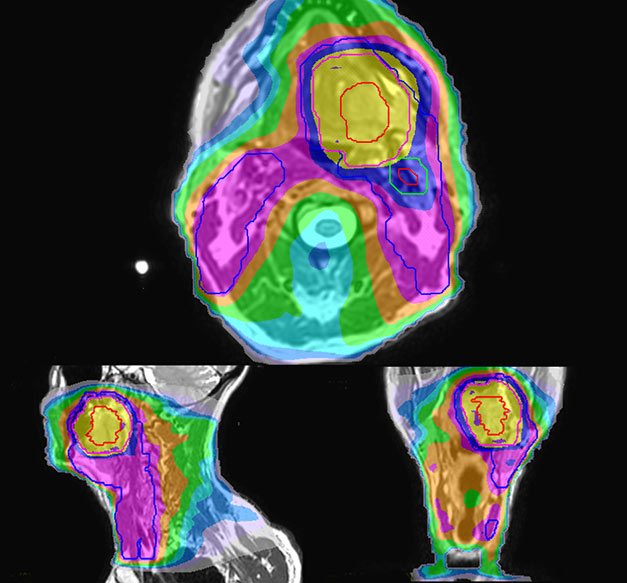

Simulation imaging

LaTour 3D Stir mDIXON MRI scans

T2W 3D, 3D STIR and mDIXON MRI scans.

Comparison of CT simulation scan

Comparison of CT simulation scan (left) and T2W 3D MRI (right)